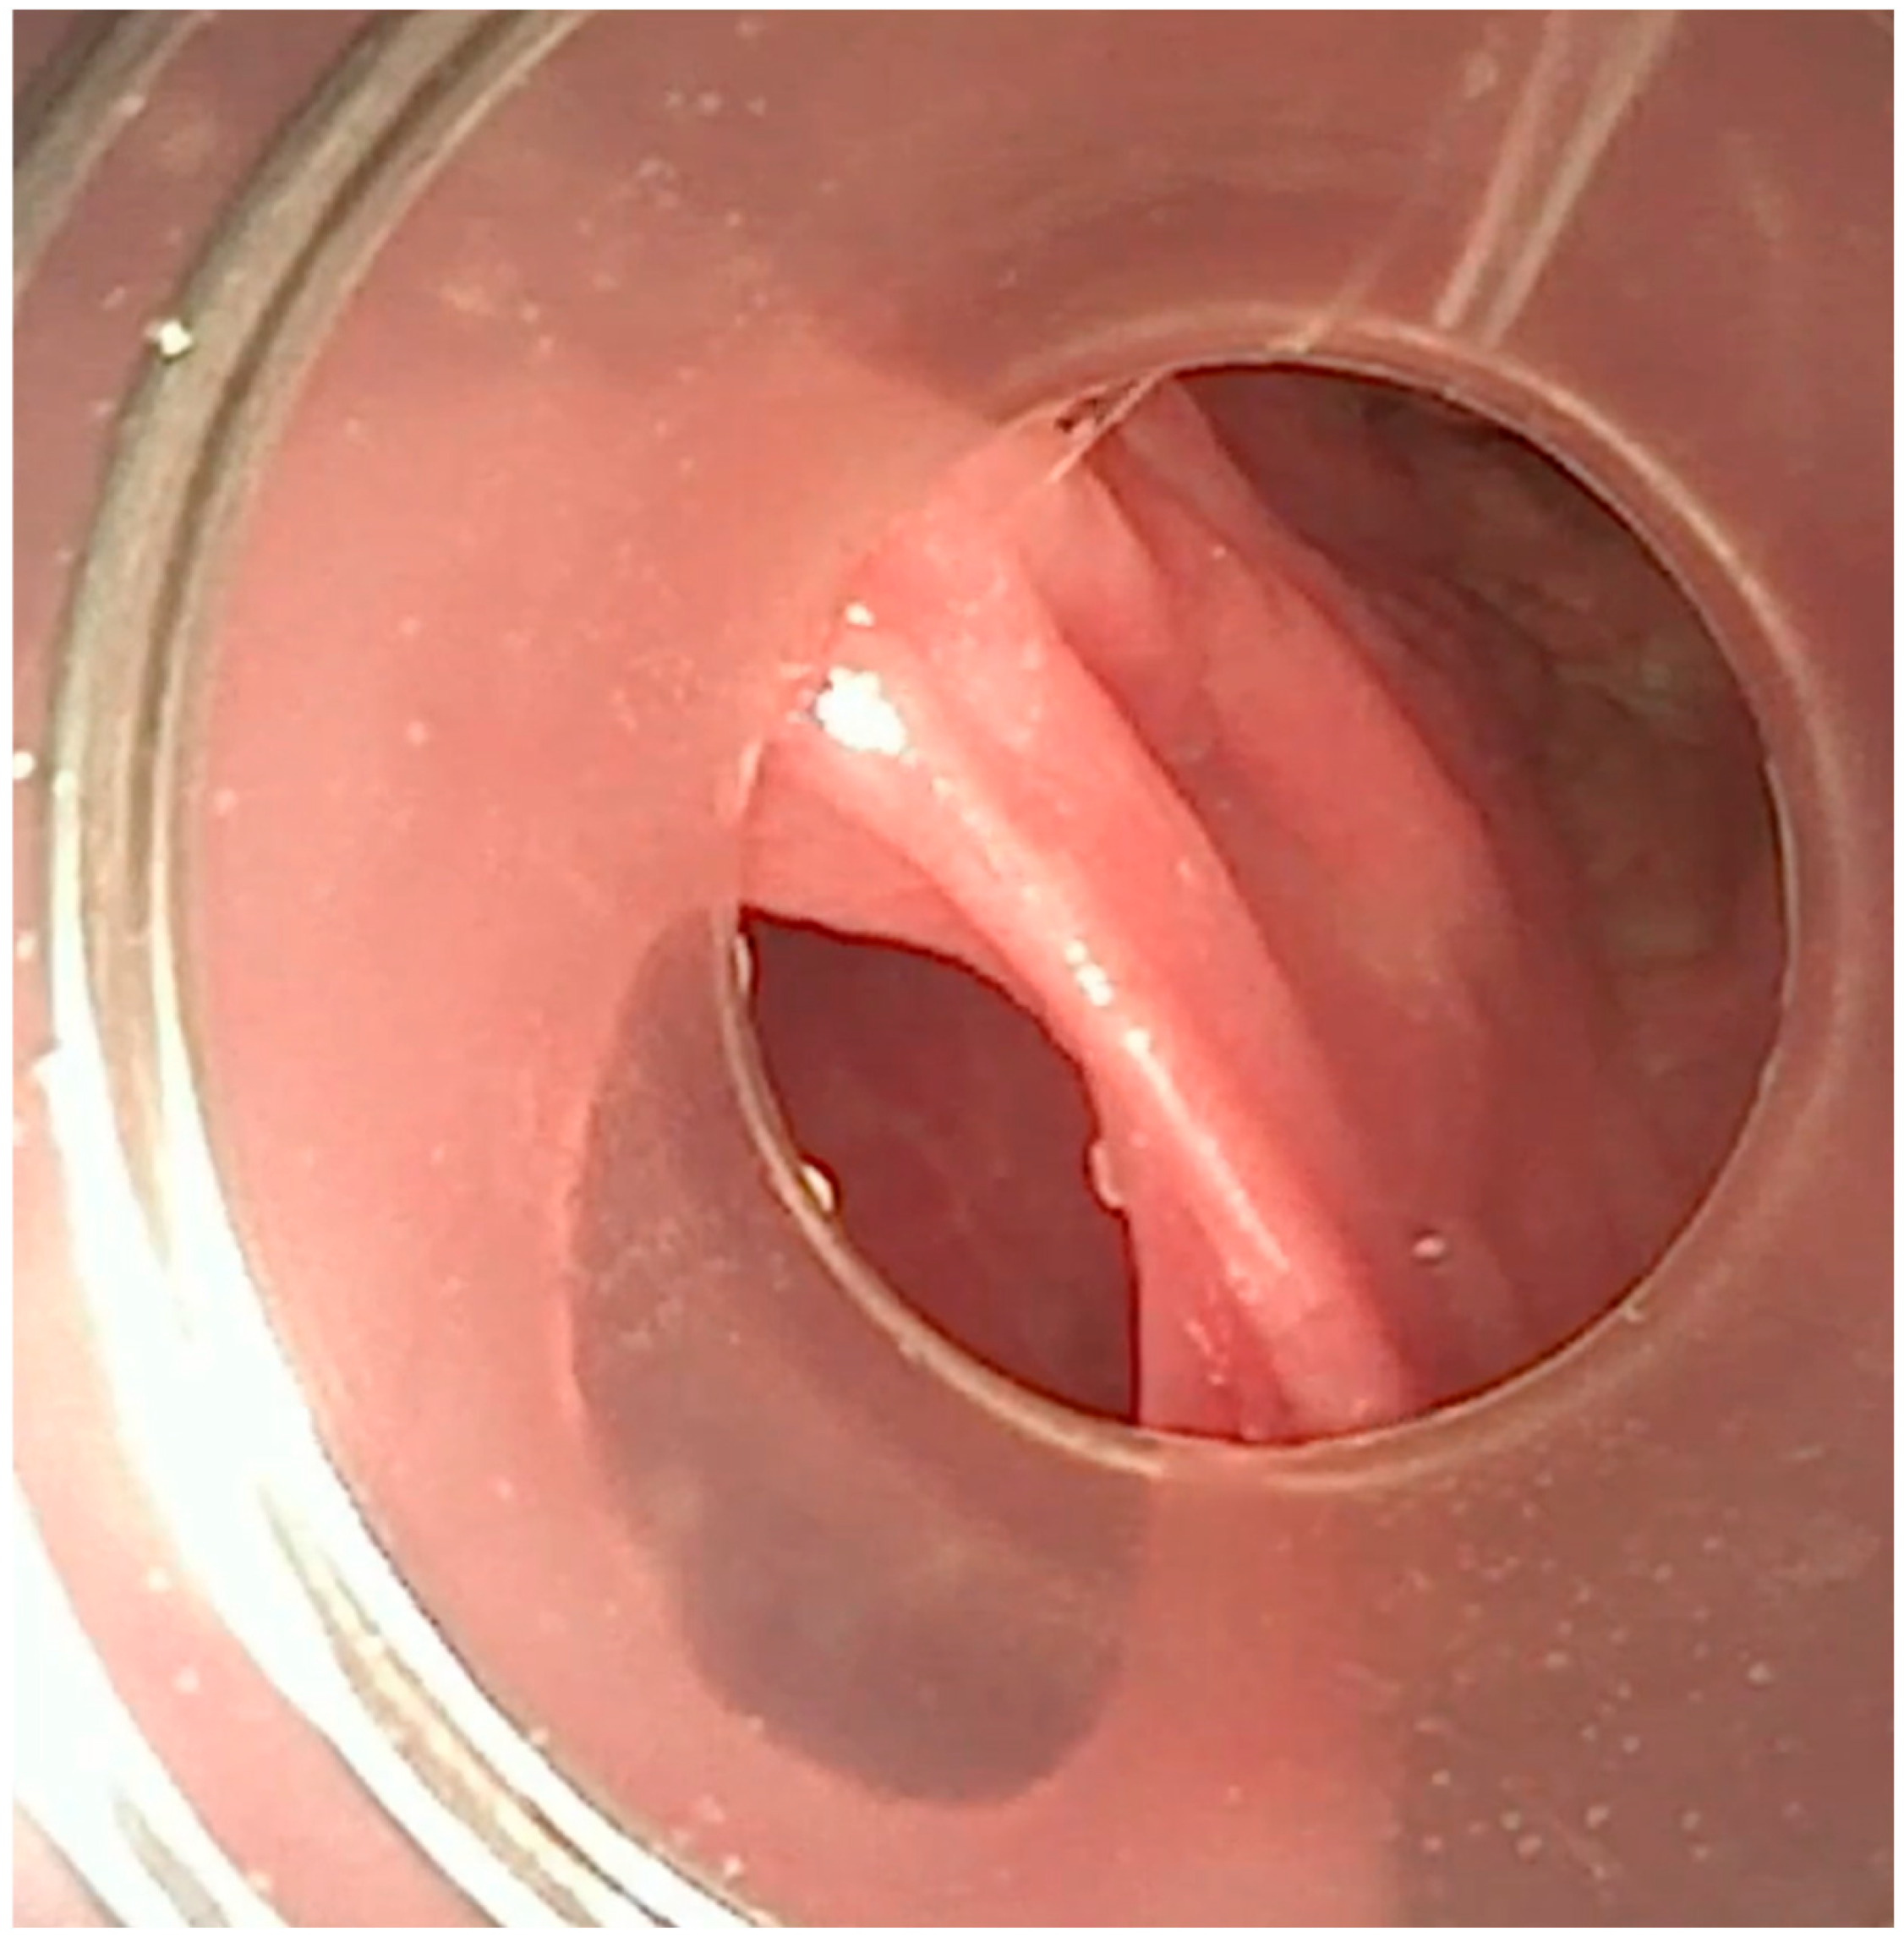

A flexible bronchoscopic examination under general anesthesia demonstrated extensive ulcerative granulation tissue distal to the tracheostomy cannula obstructing 60% of the tracheal lumen (Figure 1). To address this finding, the tracheal cannula was replaced with a longer cannula extending beyond the granuloma. The insertion of the extended cannula was performed under bronchoscopic guidance. A subsequent follow-up evaluation at six months revealed a substantial reduction in the granuloma’s size.

Figure 1. Tracheoscopic visualization of an obstructing granuloma at the distal end of the tracheostomy cannula.